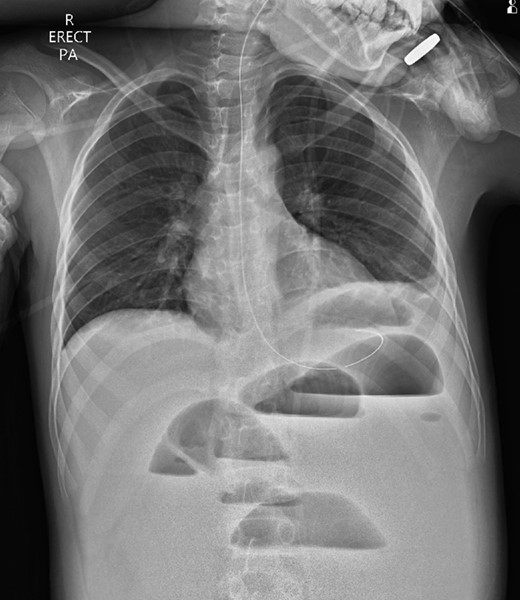

A 10-year-old boy presented unwell with generalized peritonitis after 3 days of abdominal pain, nausea and anorexia. He had a low-grade fever but all other vitals were within normal limits. Blood tests showed a raised white cell count of 16 × 109 with neutrophilia and raised C-Reactive Protein of 127 mg/l. Laparoscopy revealed generalized purulent peritonitis secondary to perforated appendicitis. Appendicectomy was performed and the appendiceal stump was secured. Lavage of the abdomen was performed with a minimum of four litres of warmed normal saline. Fluid was suctioned, an abdominal drain was placed and the pneumoperitoneum was deflated. By the second postoperative day, he developed an ileus with persistent vomiting (Fig. 1). This was managed conservatively with nasogastric intubation, bowel rest, electrolyte replacement and fluid therapy. It became clear by the fifth postoperative day that the patient had intestinal obstruction. On examination, he had a distended abdomen, with intractable nausea and vomiting. Blood tests revealed a normal white cell count and potassium remained at 3.3 despite supplemental intravenous replacement. Abdominal X-ray revealed a small bowel obstruction and he was taken back to theatre for an emergency laparotomy (Figs 2 and 3). A small bowel volvulus was discovered, with no evidence of intestinal malrotation. The volvulus involved a segment of distal jejunum to proximal ileum causing complete small bowel obstruction.

Erect chest radiograph on postoperative day 2 suggestive of small bowel ileus.